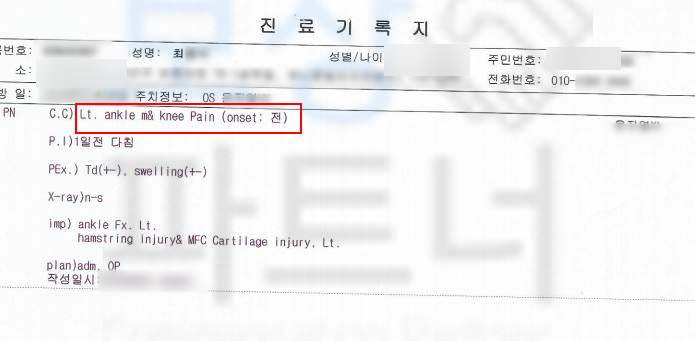

최@@님은 등산 중에 넘어지는 사고를 당하셨습니다.

위 사고로 발목 통증이 계속되자 정형외과에 내원한 의뢰인은

족관절 내과 골절 및 관절 내 유리체에 손상을 입었고 s8250 핀 고정술을 받아야 했습니다.